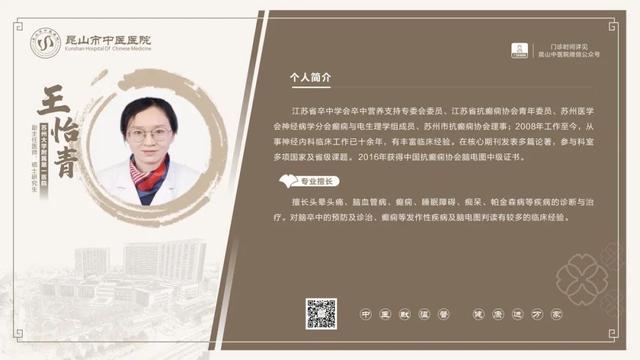

6��23��-6��29��������ר�ҳ���һ����

������鿴��ͼ���Ե���ʵ�ʳ���Ϊ��

6��23��-6��29�������dz���ר�ҽ���